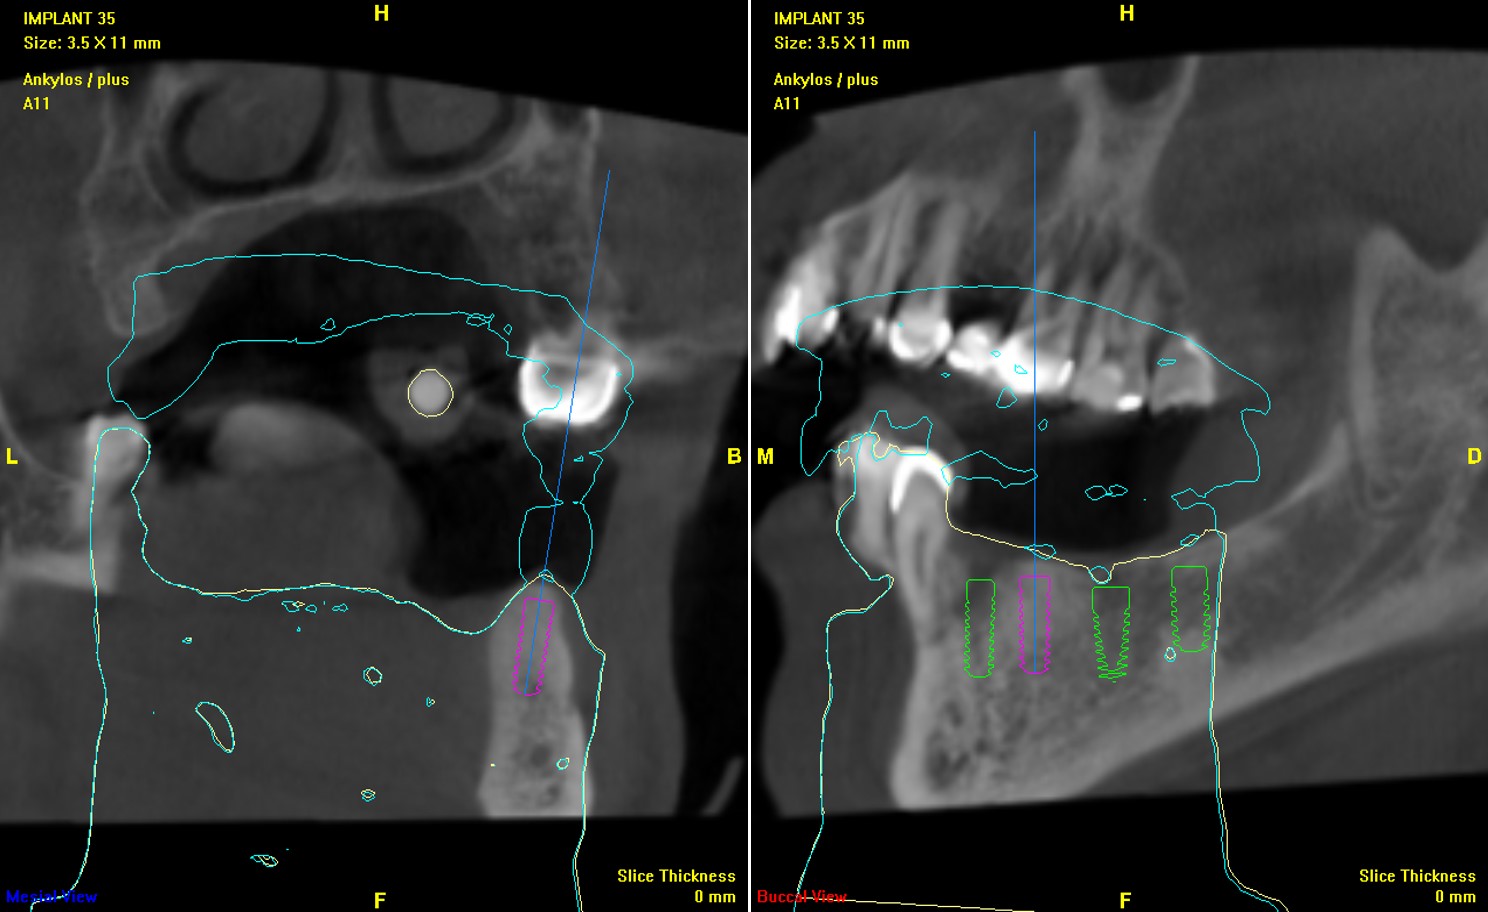

植體位分析:#34,頰側骨缺損

植體位分析:#35

植體位分析:#36

植體位分析:#37